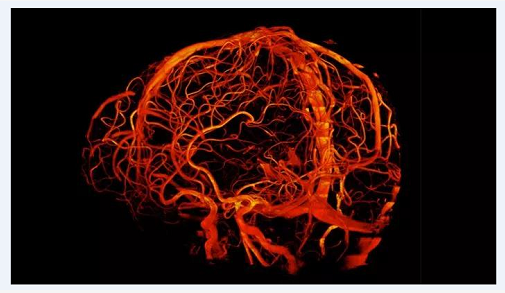

澳大利亚昆士兰大学的7T磁共振成像扫描仪产生大脑扫描图像

图源:昆士兰大学高级成像中心

7T MRI 设备目前在参与Human Connectome Project,上图是该project测绘的脑白质图片之一